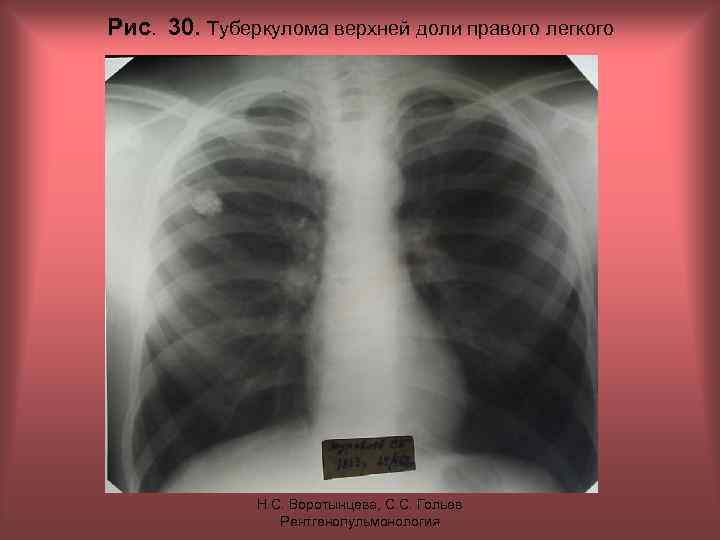

Рис. 30. Туберкулома верхней доли правого легкого Н. С. Воротынцева, С. С. Гольев Рентгенопульмонология